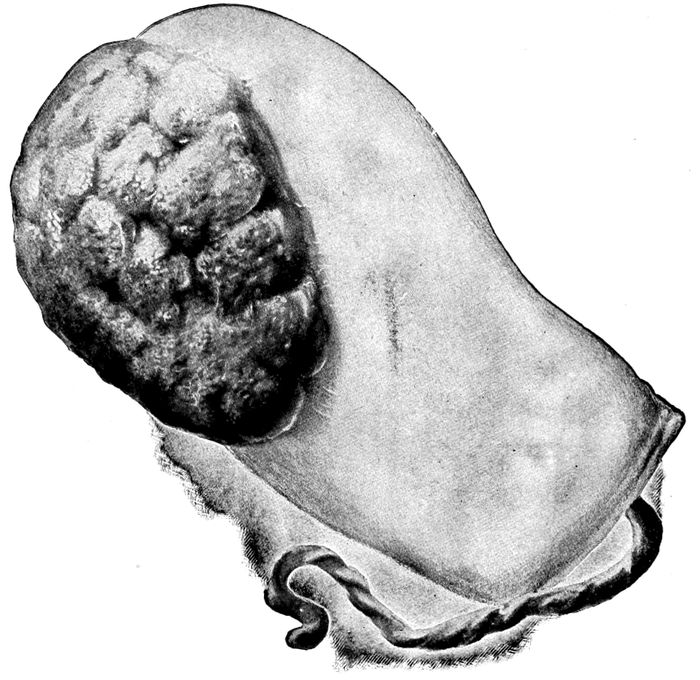

Maternal surface of the placenta and membranes |

Fig. 17.—Maternal surface of the placenta and membranes. The cord protrudes from the cavity which held the fœtus. (Edgar.)